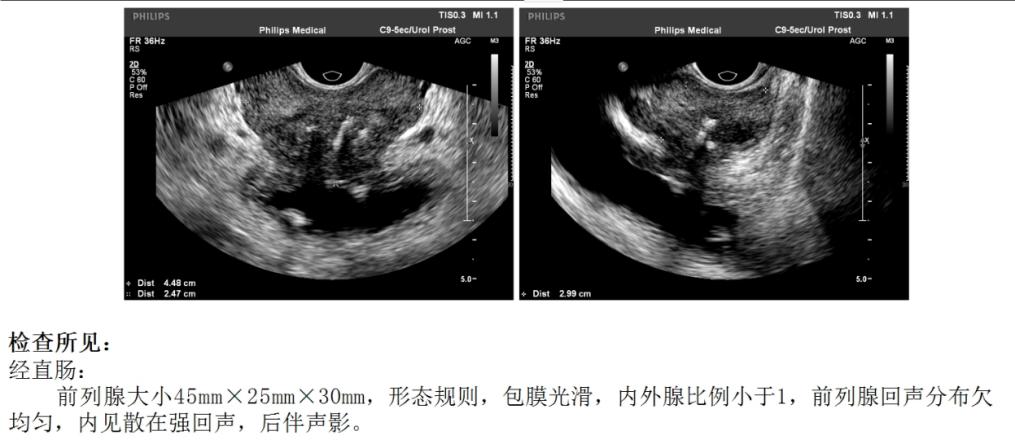

李大爷2月前在家中出现反复尿痛,李大爷认为是普通的尿路感染,自己在药店里买点消炎药服用,吃完药后症状稍有改善,不过后面又会发作,同时伴有尿频、尿急、夜尿增多等症状,这段时间折磨的李大爷非常痛苦。肉眼血尿和发热是没有的,李大爷到当地医院做了泌尿系彩超检查发现前列腺增生和膀胱结石,尿常规基本正常,前列腺肿瘤标记物(PSA)正常,给予坦索罗辛缓释片等药物对症治疗后症状没有明显改善。为了进一步诊治,李大爷又到我门诊来复诊,我觉得反复尿痛可能和膀胱结石有关,建议李大爷住院做个膀胱镜,顺便把结石取出来。李大爷和家属都表示认同,我们便给李大爷安排了住院。

不做不知道,李大爷在做膀胱镜检查时发现了膀胱里有多发肿瘤,彩超里显示的强回声其实是肿瘤表面的钙化灶,因为肿瘤是扁平状的,所以彩超检查没有发现异常凸起,而膀胱镜直视下膀胱内的情况就一清二楚了。我们利用膀胱电切镜将肿瘤完整的切除下来,同时也将表面的钙化灶同时清除,肿瘤标本送去做病理化验。手术过程很顺利,也没有明显出血,术后留置了三腔导尿管并进行膀胱冲洗,李大爷的前列腺稍偏大,没有膀胱颈抬高,术后给予多沙唑嗪联合非那雄胺治疗。术后第五天,李大爷顺利拔除导尿管后出院。